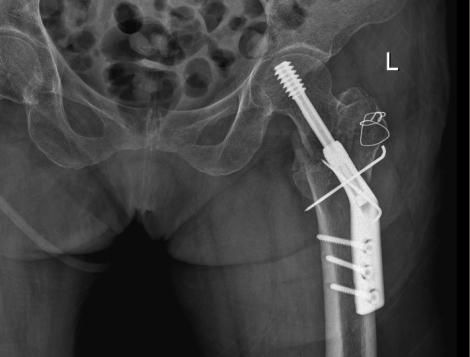

△術前

經過CT檢查發現老人家的左股骨頸骨折。此外還伴有老年性骨質疏松、高血壓病、低鈉低鉀血症等疾病。骨科吳志斌主任随即請内科、麻醉科專家會診。予監控血壓、血糖,抗骨質疏松、營養心肌等對症治療。待患者病情穩定、可耐受手術後進行手術治療。

吳志斌主任通過CT+三維重建先行拟定詳細手術方案,提前做了精心準備。根據患者的年齡特征,爲其選擇最佳的半髋置換方案,并采用雙動人工股骨頭,提高活動範圍,減少髋臼磨損。

10月20日,老人家被送進了手術室行左側人工股骨頭置換術。吳主任根據方案按部就班地實施手術,娴熟地完成每一個手術步驟,精心地把控每一個細節,确保髋部良好的活動性和穩定性,以及雙下肢等長。整個手術過程非常流暢、一氣呵成。術中患者各項生命體征平穩,術後平安返回病房。